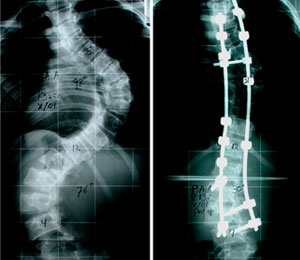

Cifosis rígida toracolumbar (Enfermedad de Scheuermann): varón de 20 años, consulta por dolor toraco lumbar intenso, realizo 4 anos de terapia física y rehabilitación sin éxito. 10 meses Post-operado, se tuvo que realizar varias osteotomías de columna, actualmente sin dolor, realiza actividades cotidianas sin limitaciones.